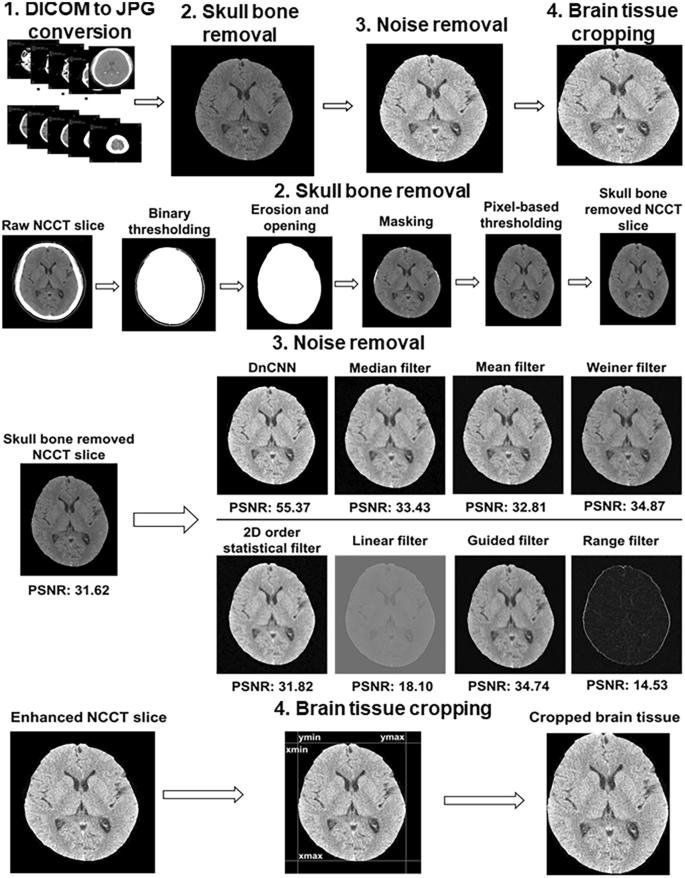

The identification of the presence of ischemic lesion on raw NCCT which was taken in the early stage after ischemic stroke using DL is challenging due to low contrast quality, presence of skull bone, and in-built noise artifacts. Therefore, the following preprocessing steps were used (Fig. 1) before DL model design to improve the NCCT image quality and remove unwanted information.

Procedures of NCCT image preprocessing. The upper part shows overall preprocessing steps starting from 2D NCCT slices construction to brain tissue cropping. The next part conveys the intermediate-steps used for skull-bone removal. A comparison of PSNR for different noise removal algorithms are presented in the 3rd part. The final part displays the selection of rectangular non-brain tissue region for cropping of the exact brain tissue part. NCCT non-contrast computed tomogram, 2D two dimensions, PSNR peak-to-signal noise ratio.

Removal of skull bone

Bony skull and falx calcification were removed with the preservation of brain tissue. First, binary thresholding was used over raw NCCT to get the outer part of skull. Second, morphological operations including erosion and opening were performed to remove falx calcification and outer brain region (mainly skull). Third, masking operation was carried out to obtain the exact brain tissue. Finally, skull bone was completely removed after applying the pixel-based thresholding. The automatic algorithm of skull bone removal was designed by using MATLAB R2019a (https://www.mathworks.com/products/new_products/release2019a.html).

Noise removal and image enhancement

In the processing of digital images, the amount of internal in-built noise is always unknown. Therefore, the amount of known noise needs to be added before noise removal. In the case of NCCT slices, the Gaussian noise is mostly preferred for addition10. The added noise affects the internal pixel characteristics of the original image, especially the mean and variance factors. Hence, we added the Gaussian noise with the default value of mean = 0 and variance = 0.001. The amount of noise was quantified using the concept of Peak-to-Signal Noise Ratio (PSNR)11. Mathematically, the PSNR value is inversely proportional to the amount of noise. The higher the PSNR value; the less the presence of noise in the image, implying the image is more enhanced and noise-free. Initially, in the processing of NCCT slices, the noise quantification using PSNR value was measured by passing the NCCT slices before and after the noise addition. In this instance, the original NCCT slices with unidentified noise obtained after skull removal acted as a reference for the known-noise added NCCT slices. To select the appropriate noise-removal method, different conventional filtering algorithms as well as denoising convolutional neural network (DnCNN) (https://www.mathworks.com/help/images/ref/dncnnlayers.html) developed by using MATLAB R2019a were compared. The quality of the noise removal was verified by comparing the measured PSNR value of the denoised slice with the original noisy slice. The original noisy slice was used as a comparable parameter to determine the improvement in the enhancement. In the present study, we used the DnCNN algorithm which could perform better with PSNR = 55.37, making the image more enhanced compared to the input NCCT slice with only skull bone removal (PSNR = 31.62).

Brain tissue cropping

To eliminate the background surrounding brain tissue, automatic cropping of brain tissue was performed by using the concept of pixel-level analysis (https://www.mathworks.com/matlabcentral/answers/397432-auto-crop-the-image). The cropping was performed as a rectangular area where the coordinates Ymin and Ymax represent the lowest and highest nonzero columns, whereas the Xmin and Xmax indicate the minimum and maximum nonzero rows in an image size of 512 × 512. In the final phase, a rectangular cropped brain tissue region was obtained using the coordinates (Xmin, Ymin): (Xmin, Ymax), (Xmax, Ymin): (Xmax, Ymax) as shown in Fig. 1.